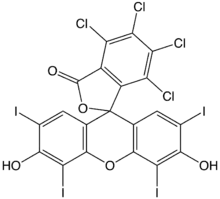

Xanthene-based sensitizers

Xanthene-based sensitizers, on the other hand, have shown successful cytotoxicity in vitro by producing reactive oxygen species after being triggered by ultrasound.[1] More research is necessary to improve its potential in vivo performance since it is quickly processed by the liver and cleared from the body.[1] Rose Bengal is a commonly used xanthene-based sonosensitizer.[1]